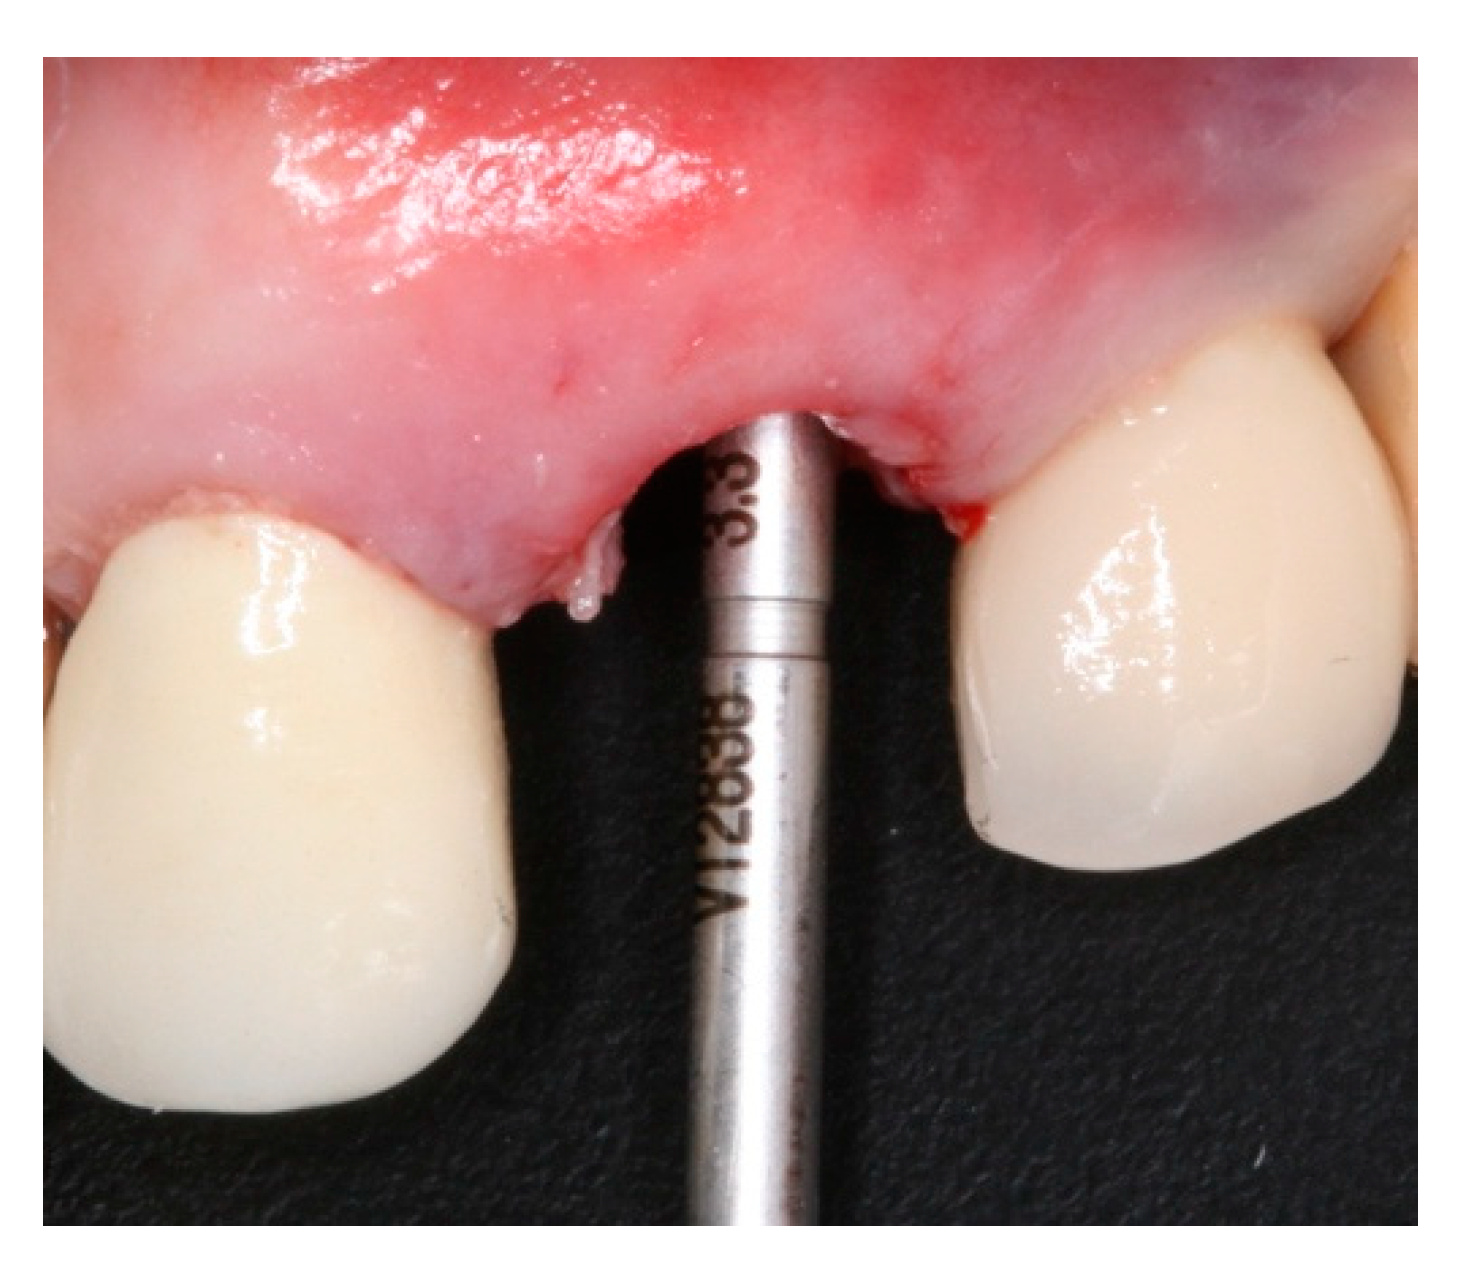

2. Materials and Methods